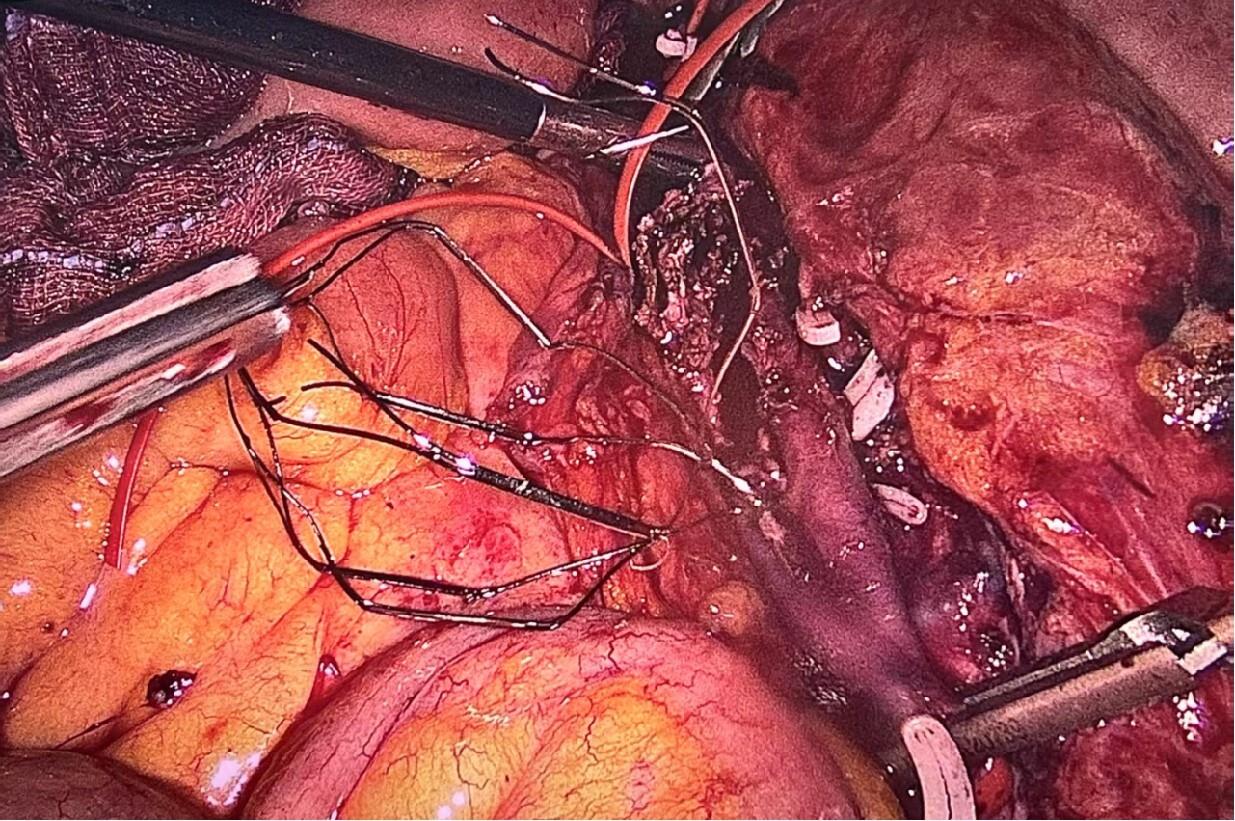

2025, 34(12):2710-2716. doi: 10.7659/j.issn.1005-6947.250520

摘要:背景与目的 下腔静脉滤器在预防深静脉血栓脱落导致肺栓塞中具有重要作用,但部分滤器因回收钩贴壁、内膜增生包裹或穿出血管壁等原因,无法经血管腔内途径取出。本研究旨在总结腹腔镜下取出下腔静脉困难滤器的手术经验,评价其安全性与可行性。方法 回顾性分析2024年3月—2025年5月在广州医科大学附属第二医院行腹腔镜下腔静脉滤器取出的12例困难滤器患者临床资料。所有患者均曾尝试经血管腔内途径取出滤器失败。根据滤器位置选择头侧或尾侧入路,经腹腔前正中途径行腹腔镜手术,记录手术成功率、手术时间、术中出血量、围术期并发症及随访情况。结果 12例患者中,伞形滤器10例,梭形滤器2例;滤器植入中位时间为3(1.3~11.5)个月。滤器主要位于肾静脉周围区域(91.7%)。11例采用头侧入路,1例采用尾侧入路。11例(91.7%)成功经腹腔镜完整取出滤器,1例因梭形滤器顶端进入肾区、血管阻断不完全致术中出血失控而中转开腹。平均手术时间为(252.8±83.2)min,中位术中出血量150(50~500)mL。所有患者术后均顺利康复出院,无腹腔或切口感染。随访(9.8±3.8)个月,未见下腔静脉血栓形成或管腔狭窄。结论 对于经血管腔内途径取出失败的下腔静脉困难滤器,腹腔镜下取出术是一种安全、有效的微创替代方案。该术式的成功依赖于合理选择手术入路、充分的滤器段血管阻断及针对不同滤器类型采取个体化取出策略,但对术者腹腔镜血管外科技术要求较高。